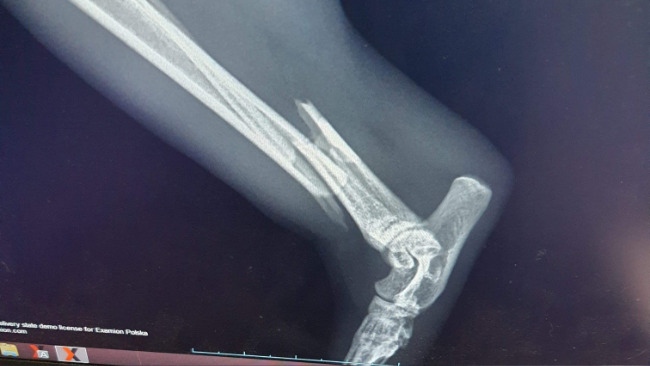

Filemona złamała łapkę.